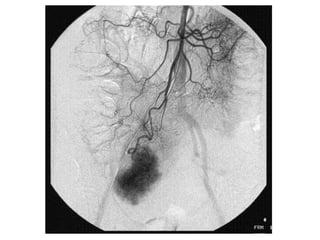

– Angiography

• Bleed rate ≥1.0ml/min

• Pros : therapeutic in same setting

• Cons : invasive, high dose radiation

• Angioembolisation